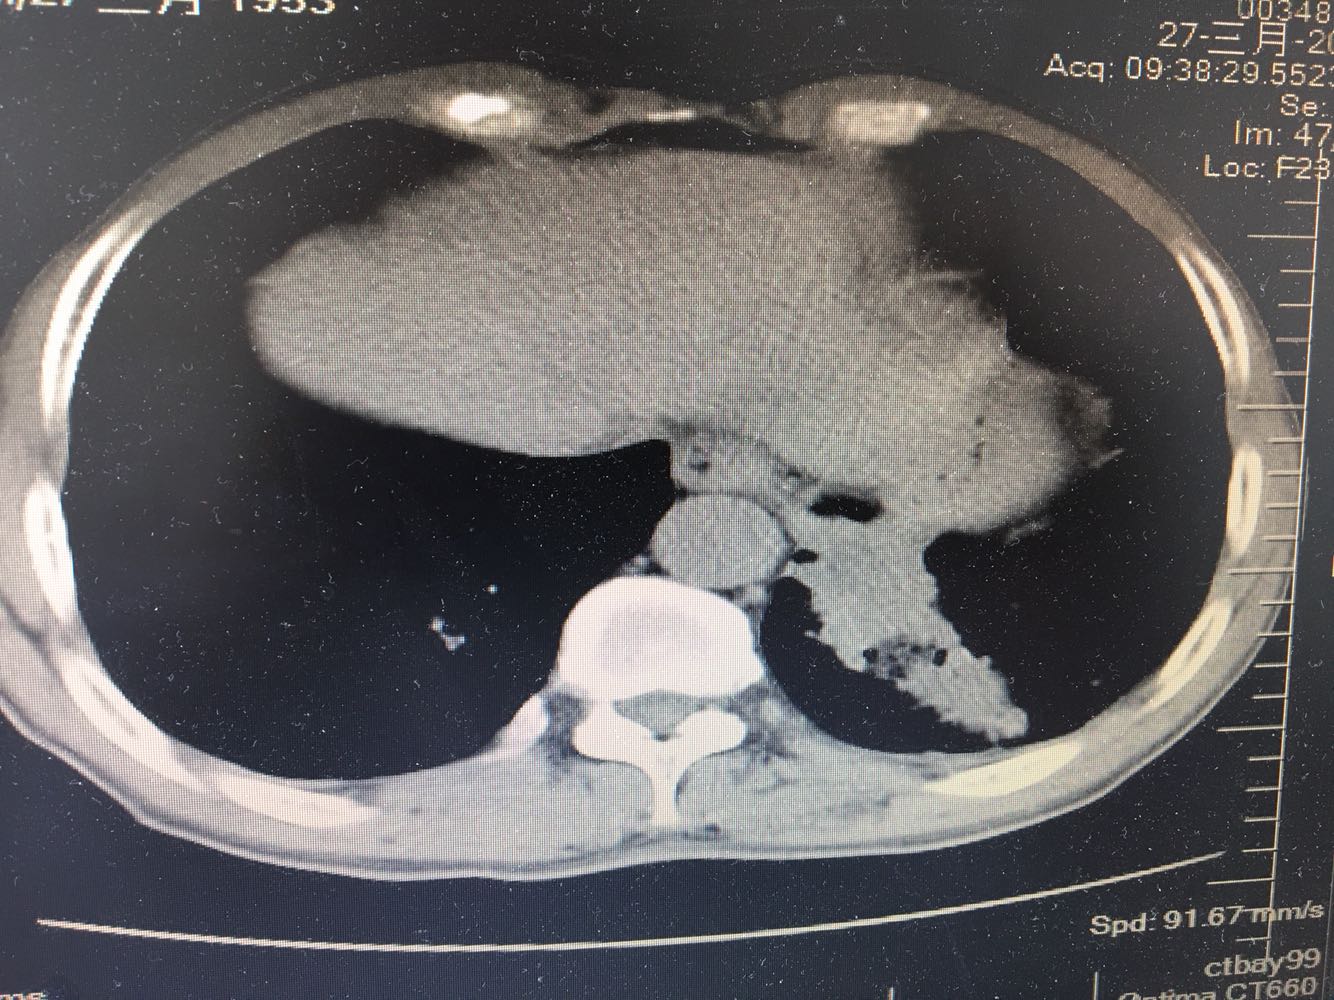

左肺下叶鳞癌

男,63岁,咳嗽1个月入院,患者自述1个月前无诱因咳嗽,阵发性干咳,无痰,时有血丝,无发热,左胸痛,活动后气短,静滴头孢13天无好转,门诊查肺CT后以 肺占位收入我科,病来饮食睡眠可,体重明显下降。既往疝气术后1年,吸烟史30年,每日1包。

左肺癌

左肺中央型肺癌,是否可以手术,还是化疗,放疗,靶向治疗?